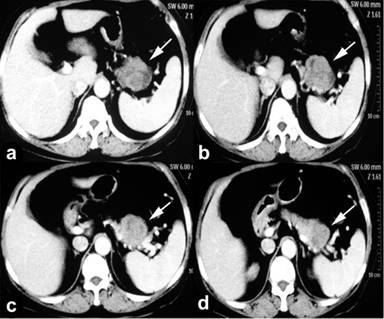

A sixty-six-year-old woman was admitted to our hospital who had suffered abdominal pain and nonspecific nausea for almost 40 days. Physical examination showed a vaguely palpable left upper abdominal mass with mild deep tenderness. Laboratory data including tumor marker (CA 19-9, CA 153, CEA, etc.) was normal. Abdominal ultrasound, magnetic resonance imaging (MRI) and computed tomography (CT) revealed a clear-bordered cystic–solid mass with heterogeneous density involving the tail of the pancreas (Figure 1). It measured approximately 4.0×5.0 cm, without any evidence of metastasis or invasion of the adjacent vessels and other tissues. We performed an en bloc distal pancreatectomy with splenectomy for radical excision, as well as regional lymphadenectomy. The postoperative pancreatic fistula and intra-abdominal abscess led to prolonged hospitalization (25 days), and was cured through percutaneous drainage and antibiotics. Gross examination revealed a 4.0×5.0 cm exophytic clear-bordered neoplasm of the tail of the pancreas containing necrotic and calcified areas, without invasion of the spleen (Figure 2). Three suspicious lymph nodes around the splenic artery and two around the splenic hilum were resected and evaluated for invasion. The lymph node involvement was not detected (0/5) and the surgical margins were negative (R0). The pathological examination revealed pleomorphism with giant cells and the spindle-shaped cells with anaplasia seen in hematoxylin and eosin (H&E) staining of tumor tissue (Figure 3). Immunohistochemical staining of tumor tissue was negative for smooth muscle actin (SMA), pancytokeratin (PCK), epithelial membrane antigen (EMA), S100, β-catenin and CD10, but weak positive for vimentin (Figure 4).

Figure 1. Computed tomography revealed a clear-bordered cystic-solid mass with heterogeneous density involving the tail of the pancreas (arrow). |

Given its aggressive biological behavior and poor prognosis, it is of prime importance to make early diagnosis for patients with undifferentiated carcinoma of the pancreas. Imaging techniques such as ultrasound, CT and MRI help in some way to explain the nature of the tumor. A clear-bordered cystic–solid mass with heterogeneous density is the most common imaging feature of undifferentiated (spindle cell) carcinoma of the pancreas. Calcification is another imaging feature when undifferentiated pancreatic carcinoma is associated with osteochondroid differentiation, although it was not obvious on CT/MRI and ultrasound in our present case. However, it is difficult to differentiate this tumor from solid-pseudopapillary tumor (SPT) of the pancreas by imaging techniques alone. Because the typical imaging presentation of SPT is also a capsulated heterogeneous pancreatic mass with cystic and solid components [9]. Calcification may be also present in some cases of SPT [10]. Endoscopic ultrasound-guided fine needle aspiration (EUS-FNA) is increasingly used for pre-operative diagnostic yield of pancreatic mass [11], including undifferentiated carcinoma and SPT of the pancreas [6, 10]. However, EUS-FNA is an invasive procedure, and the operators' experience plays an important role in quality of FNA biopsy thereby determining the correct diagnosis of the tumor. In addition, EUS-FNA has limits of the risk of tumor dissemination and scant sampling of the lesion, especially for cystic–solid lesions with fluid in it. Therefore, preoperative EUS-FNA is not routinely performed for evaluation of a pancreatic mass with mixed solid and cystic components, especially when it is highly suspicious of malignancy basing on imaging [12, 13]. Preoperative EUS-FNA was not used in our case. Pathological confirmation seems to be the reliable way to prove the diagnosis of undifferentiated carcinoma of the pancreas. However, SPT with high-grade malignant transformation shares similarities in histological presentation with undifferentiated carcinoma of the pancreas, including nuclear atypia and spindle cell components [12, 14]. Immunohistochemical stains for CD10, β-catenin, vimentin, synaptophysin and chromogranin are helpful to differentiate them [3]. Of these, CD10, β-catenin and vimentin are the most consistently positive markers for SPT. Nevertheless, vimentin has previously been reported to be positive in both SPT and undifferentiated carcinoma of the pancreas [3, 10, 15]. Immunohistochemical staining of the tumor in our case were negative for both CD10 and β-catenin, but weak positive for vimentin. Combining with the findings in the HE staining, we excluded the diagnosis of SPT and made a diagnosis of undifferentiated (spindle cell) carcinoma of the pancreas with focal osteochondroid differentiation.